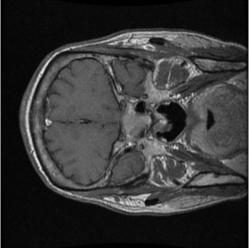

Numerous coreset selection works (Huang et al., 2023; Loshchilov and Hutter, 2015; Marion et al., 2023; Park et al., 2024; Paul et al., 2022; Xia et al., 2022; Yang et al., 2023a) have explored various criteria for identifying important data samples, including geometry distance (Sener and Savarese, 2017; Welling, 2009), uncertainty (Coleman et al., 2019), loss (Toneva et al., 2018; Paul et al., 2021), decision boundary (Ducoffe and Precioso, 2018; Margatina et al., 2021), and gradient matching (Mirzasoleiman et al., 2020). However, most of these methods have been validated mainly on natural image datasets, such as CIFAR-10, CIFAR-100 (Krizhevsky et al., 2009), and not extensively on medical datasets. The applicability of those methods for medical image datasets are under exploration, given the unique characteristics of medical images. Compared to natural image datasets, the intra-class variation and inter-class similarity of medical image datasets (Song et al., 2015) pose specific challenges to coreset selection. On the one hand, in medical imaging, samples within the same category can exhibit significant differences, making it difficult to capture consistent features for each class. This variation largely comes from the diversity in disease manifestation across patients and discrepancies in imaging conditions. On the other hand, the challenge of inter-class similarity arises when images representing different diseases exhibit similar visual characteristics. fig. 6 provides a more straightforward demonstration of this characteristic. These factors contribute to the complexity of medical image analysis and underscore the need for sophisticated coreset selection methods that can effectively address these challenges.

Despite the substantial progress, integrating deep learning into medical imaging is fraught with challenges (Ker et al., 2017). The effectiveness of DL in this context is largely dependent on the availability of large, well-annotated datasets tailored for specific tasks and reliant on advances in high-performance computing. The necessity for vast complex datasets introduces complications such as inconsistencies in data quality, arising from variations in imaging equipment and protocols. Moreover, the extensive volume of medical data demands significant computational resources, posing logistical challenges for efficient processing (Zhou et al., 2021). Additionally, the inherent heterogeneity of medical images, characterized by a multimodal probability distribution, complicates the model training process by requiring algorithms capable of handling diverse visual features and patterns within the data. Another issue is the inter-class similarity and intra-class variation, as depicted in fig. 6, where different diseases may appear similar, and the same disease may present differently across patients.